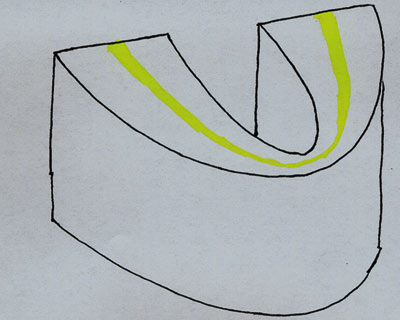

Panoramaradiografi bygger som sagt på tomografiprincippet, hvor kun objekter/strukturer, som befinder sig i skarphedszonen (omdrejningsområdet mellem røntgenkilde og billedreceptor), bliver afbildet skarpt og identificérbart. Objekter/strukturer, som befinder sig uden for skarphedszonen, bliver afbildet uskarpe og forvrængede (med distorsion). De fleste panoramaapparater anvender en skarphedszone, som er hesteskoformet med et meget smalt (ca. 10 mm) frontområde og et noget bredere (ca. 25 mm) sideområde (Fig. 2). Positioneringen af patienten i forhold til apparatets skarphedszone vil være afgørende for, hvordan tænder og kæber gengives på det færdige billede, og fotografens forståelse for panoramateknikken er ofte afgørende for opnåelse af gode panoramaoptagelser. Forståelse for panoramateknikken er også en forudsætning for at kunne identificere fejl og korrigere disse.

Fig. 2. Panoramaapparatets hesteskoformede skarphedszone.